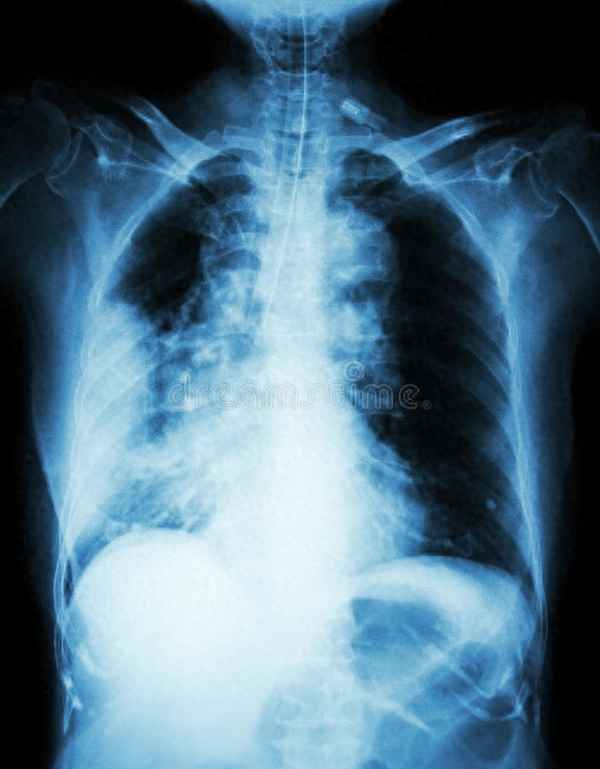

首先,我们要明白什么是肺部肿块。肺部肿块或结节,是一个影像学的术语,指影像学检查(包括 X 线、CT 等)时所看到密度偏高的类圆形或不规则阴影。它不能确定具体的性质,只能描述其大小、位置、形态、边缘、内部结构等特征。一般来说,直径小于 3cm 的称为肺结节,大于 3cm 的称为肺肿块。

· 肺炎性病变:最为常见的原因之一,指由于细菌、病毒、真菌等微生物感染引起的肺部炎症。这种情况下的肺部肿块,一般会伴有发热、咳嗽、咳痰等症状,经过抗生素治疗后,可以消退或缩小。

· 肺结核:也是常见的原因之一,指由于结核杆菌感染引起的慢性肺部感染。这种情况下的肺部肿块,一般会伴有咳嗽、咳血、盗汗、消瘦等症状,经过抗结核治疗后,可以消退或钙化。

· 肺癌:也是少见的原因之一,指由于细胞恶性增生引起的恶性新生物。这种情况下的肺部肿块,一般会伴有咳嗽、咯血、胸痛、消瘦等症状,生长快速,边缘毛刺,内部结构不均匀。